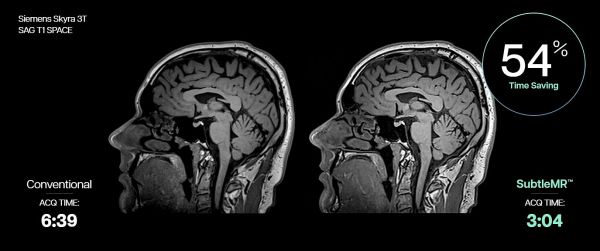

서틀엠알은 지멘스 헬시니어스 3.0T MRI ‘스카이라’(Skyra)의 뇌 시상면 방향 고해상도 3D T1 강조 영상(SAG T1 SPACE) 촬영 소요 시간(ACQ TIME)을 기존 6분 39초에서 3분 4초로 54% 단축했다. |